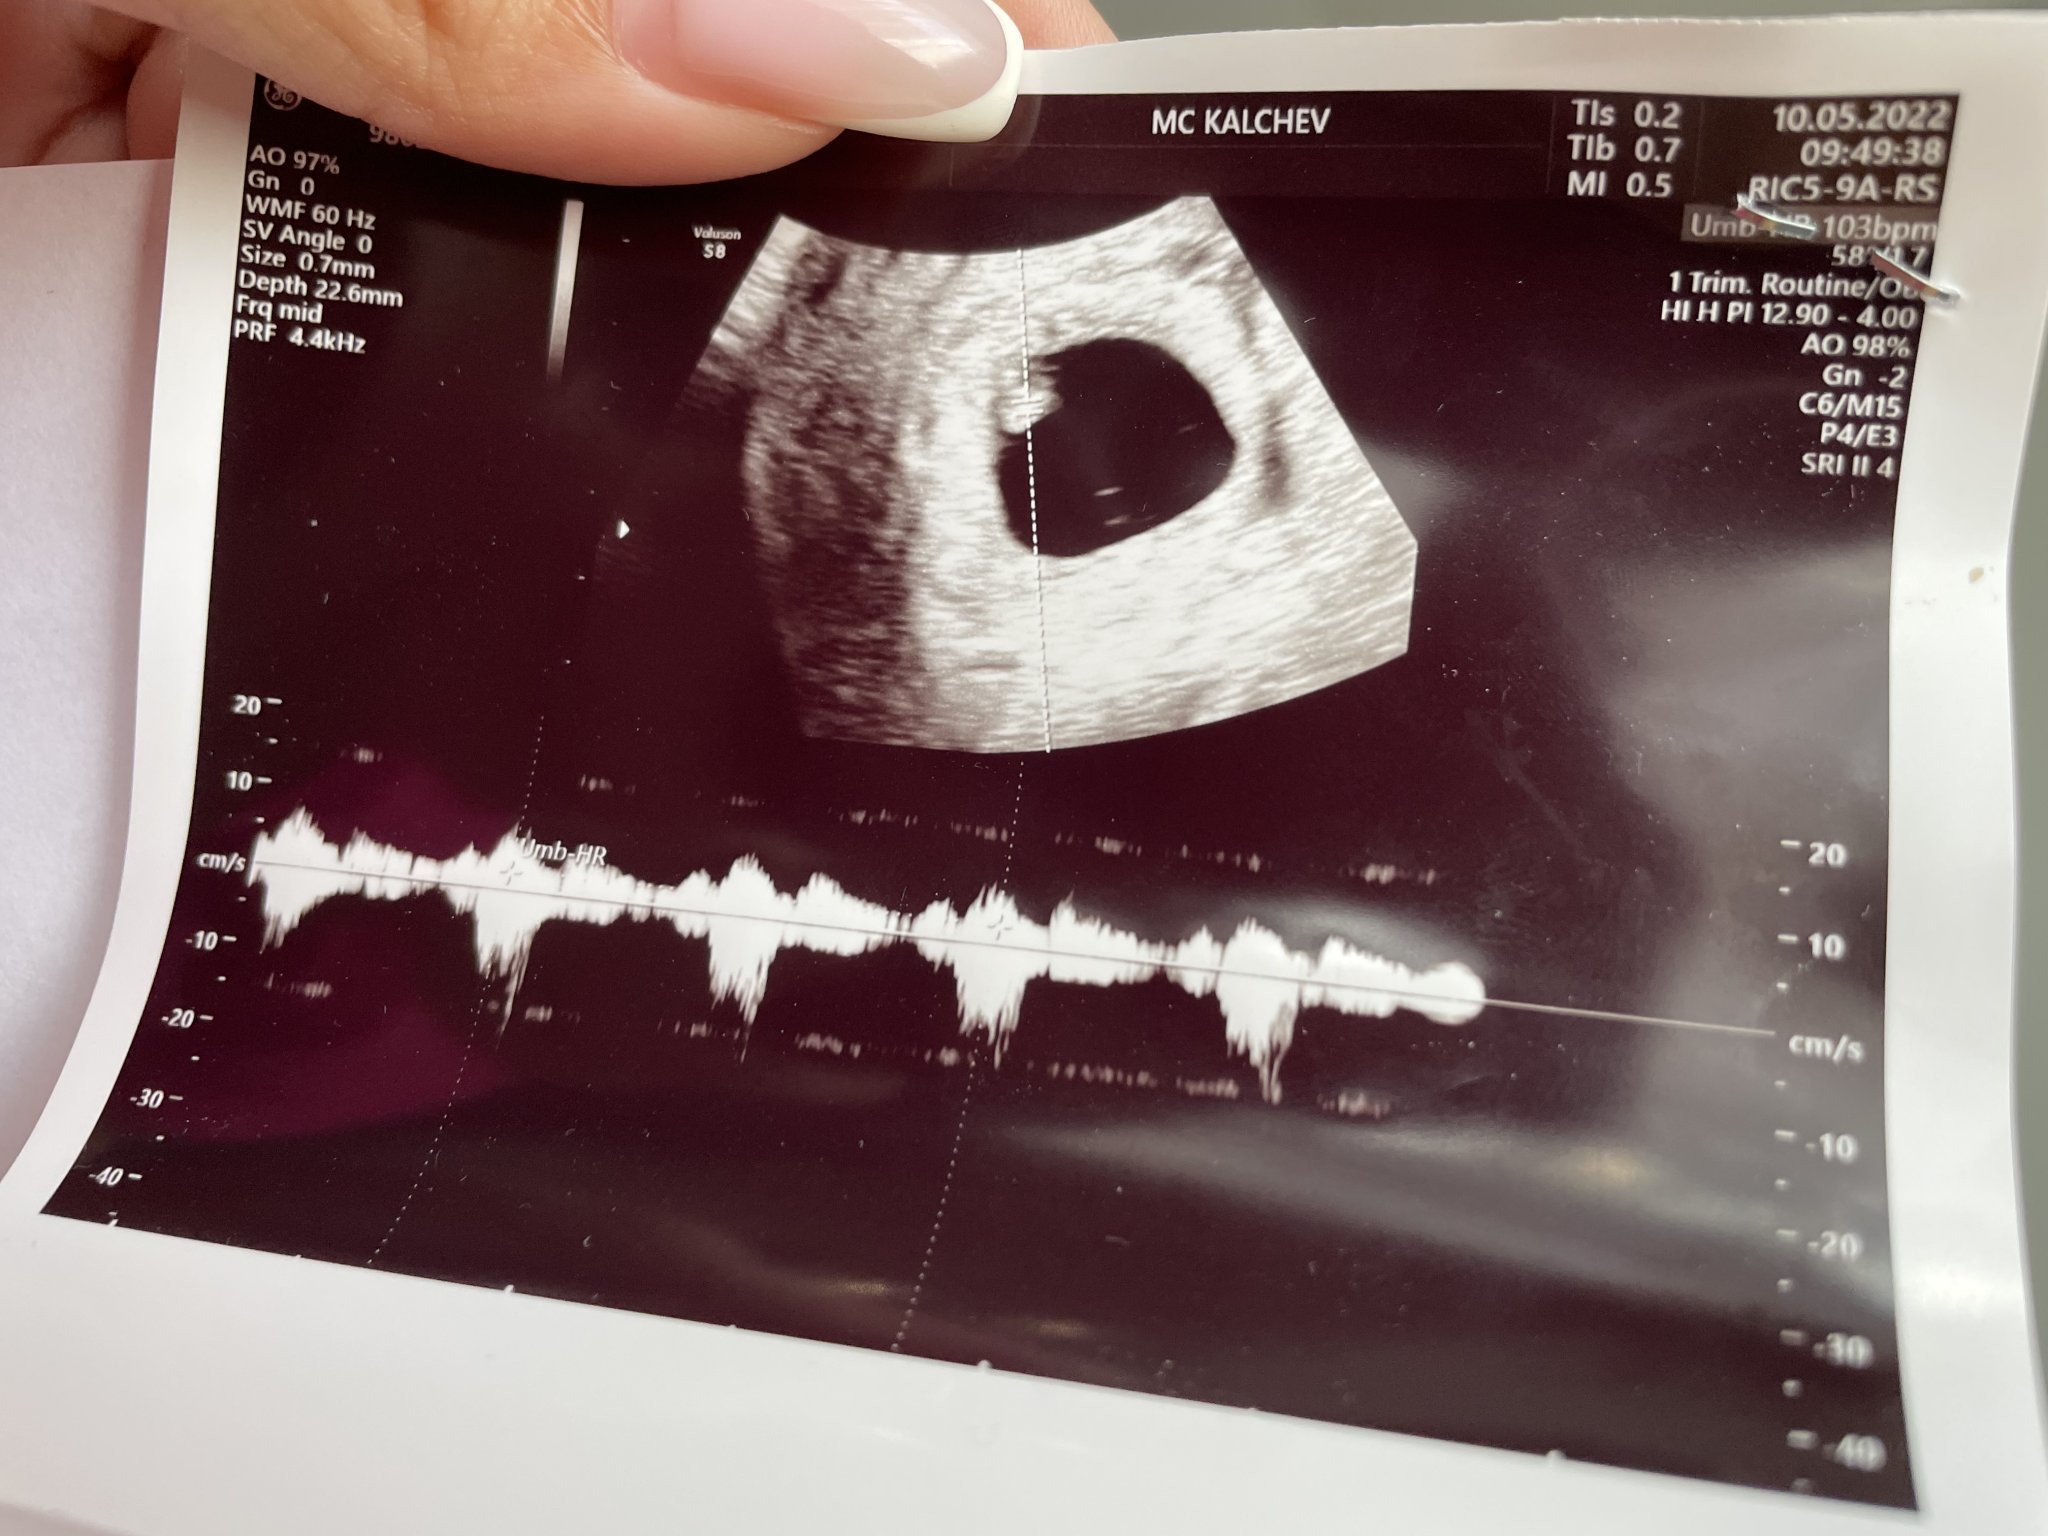

Здравейте момичета, пиша ви ъпдейт какво се случва с мен. Както беше биохимчна, извънматочна, се оказа, че са били близнаци, а сега е едничко има пулс в 6 седмица съм. Ноо имам отлепяне (не знам на хориона или на плодния сак, бях в шок като ми го каза.Прикачвам снимка ако някоя може да отговори на кое точно е отлепването, за да си чета из форума) , както и спазъм на лявата артерия в матката. На пр0гест@н съм, първите 5 ампули ми ги даде Калчев и намерих и останалите в Турция, но страшно много болят тези инжекции, мускула ми е като разкъсан не мога да ходя. Имам зацапване, каза ми че е от второто бебе, то ще си изтече. Лежа и се моля всичко да се оправи

Отлепянето е най-вероятно на плодния сак. Аз след инвитро също бях на прогестан 50 и имах лек дискомфорт,но силна болка не е била макар,че съм с нисък праг на болка.Повече почивка и спазване на терапията от док Калчев и всичко ще е наред😇🙏

Аз бях с отлепяне на хорион в 7 г.с,не знам как изглежда обаче на снимка,просто гинеколожката ми каза,че е хориона.